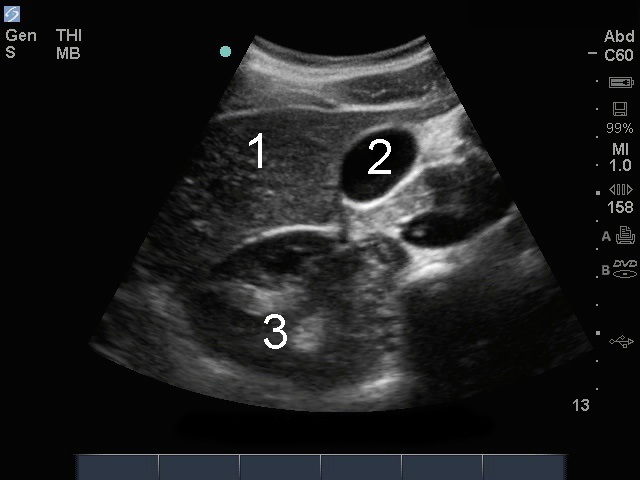

Image - Vue transverse de la vésicule biliaire

Foie

Vés. biliaire (VB)

Rein droit